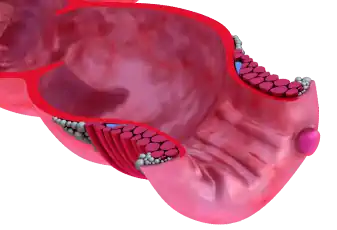

טחורים

טחורים - המדריך עם כל המידע הרפואי והמעודכן טחורים הם מעין "כריות" של כלי דם הנמצאים באופן טבעי באזור הקצה התחתון של המעי הגס ובפי הטבעת. יש להם תפקיד חשוב בהשגת אטימה טובה של פי הטבעת והרקטום, והם מסייעים בשליטה על ה